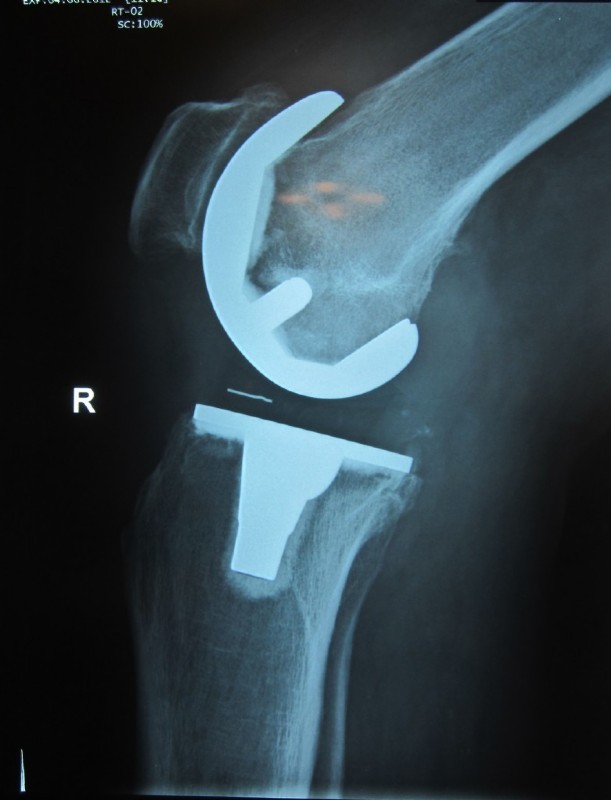

Example of a partial prosthesis

Metal parts are implanted on the thighs and plastic parts on the lower leg, which are embedded in metal components.<br></br>Plastic is also used on the rear surface of the patella with or without a metal bed.<br></br>The implant parts are anchored by either bone cement or in the case of good bone quality also without cement.